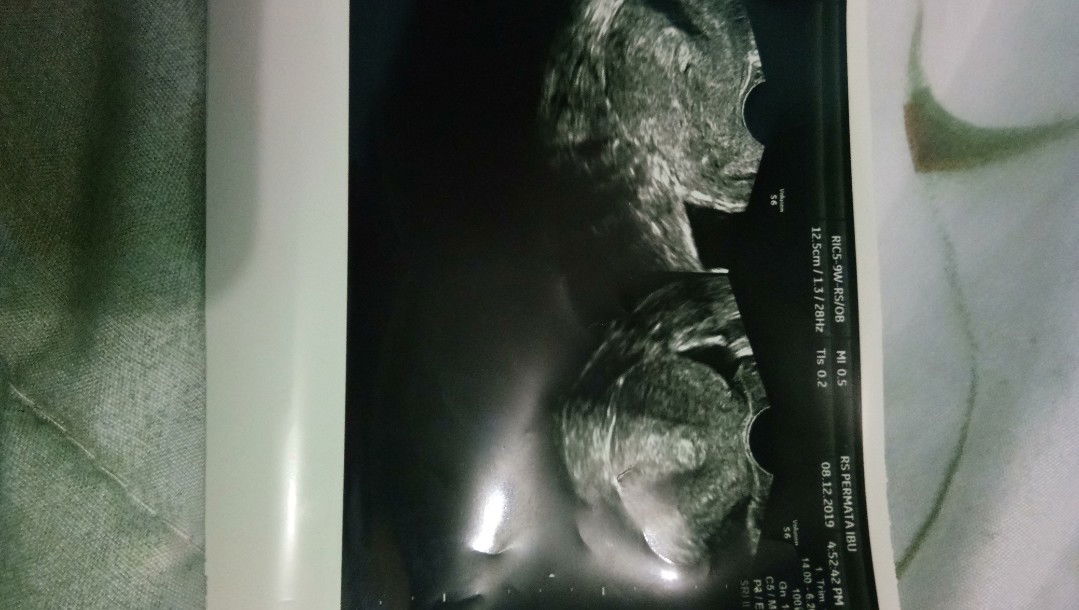

Hai bund tadi pagi saya keluar flek coklat sekitar jam 9 dan saya sedang hamil 6w3d lalu saya beberes rumah seperti biasa. Setelah beberes rumah saya tiduran saya merasa perut saya kram di bagian bawah rasanya seperti mau mens. Udh beberapa hari ini saya alami. Saya juga gak merasakan mual muntah seperti saat tau hamil. Lalu sekitar jam 12 mau solat dhuzur saya pipis dulu tapi malahan darah yg keluar dan ngucur darahnya sampe netes2. Sekitar jam 3 an saya pipis lagi sama seperti jam 12. Akhirnya saya kedokter kandungan dan dinyatakan jaringan jaringan janinnya sudah keluar tapi belom semua masih ada 1 cm lagi kalo berkembang tidak ush kuret tapi kalo segitu aja saya disuruh kuret kira2 dua minggu mendatang saya disuruh datang lagi. Saya melakukan usg transvaginal di Rs Permata Ibu. Merunut bunda2 apa saya keguguran tidak ya bund ?? Suami saya sudah sedih dan sudah menginfokan kepada kerabat dan saudara serta orang tua kabar keguguran ini ... Saya harus apa ya bund saya jadi sedih